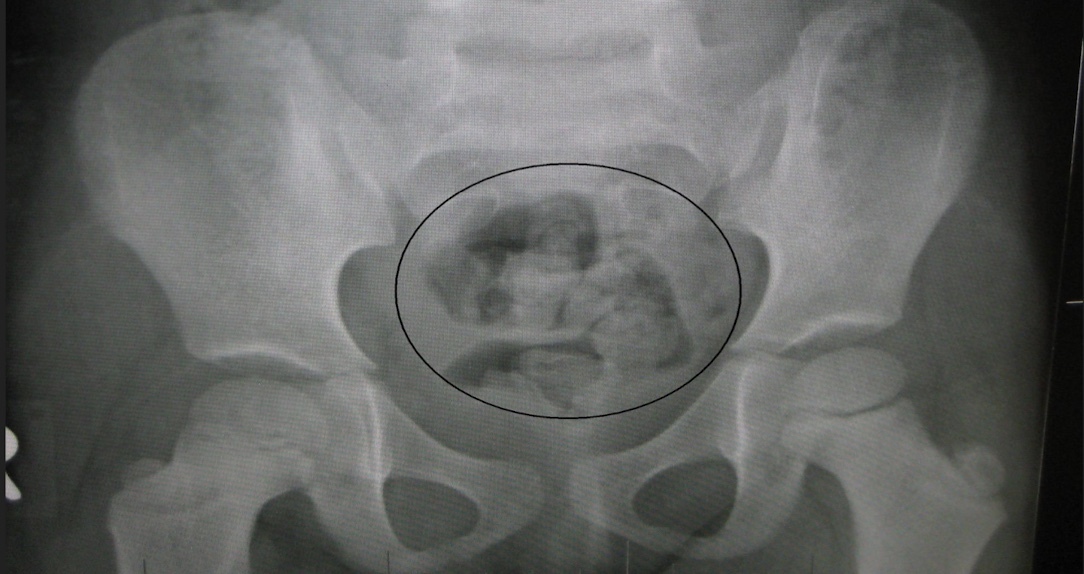

What does fecal matter look like on XRAY?

Soft opaque tissue with internal mottled air

What XRAY is good to evaluate constipation with?

AP abd/pelvis in supine position

Add on erect and lat dec if concerned for complications.